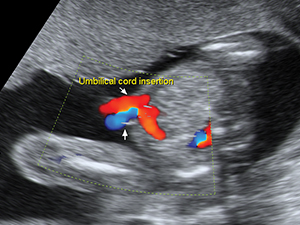

Umbilical cord insertion of the fetal abdomen